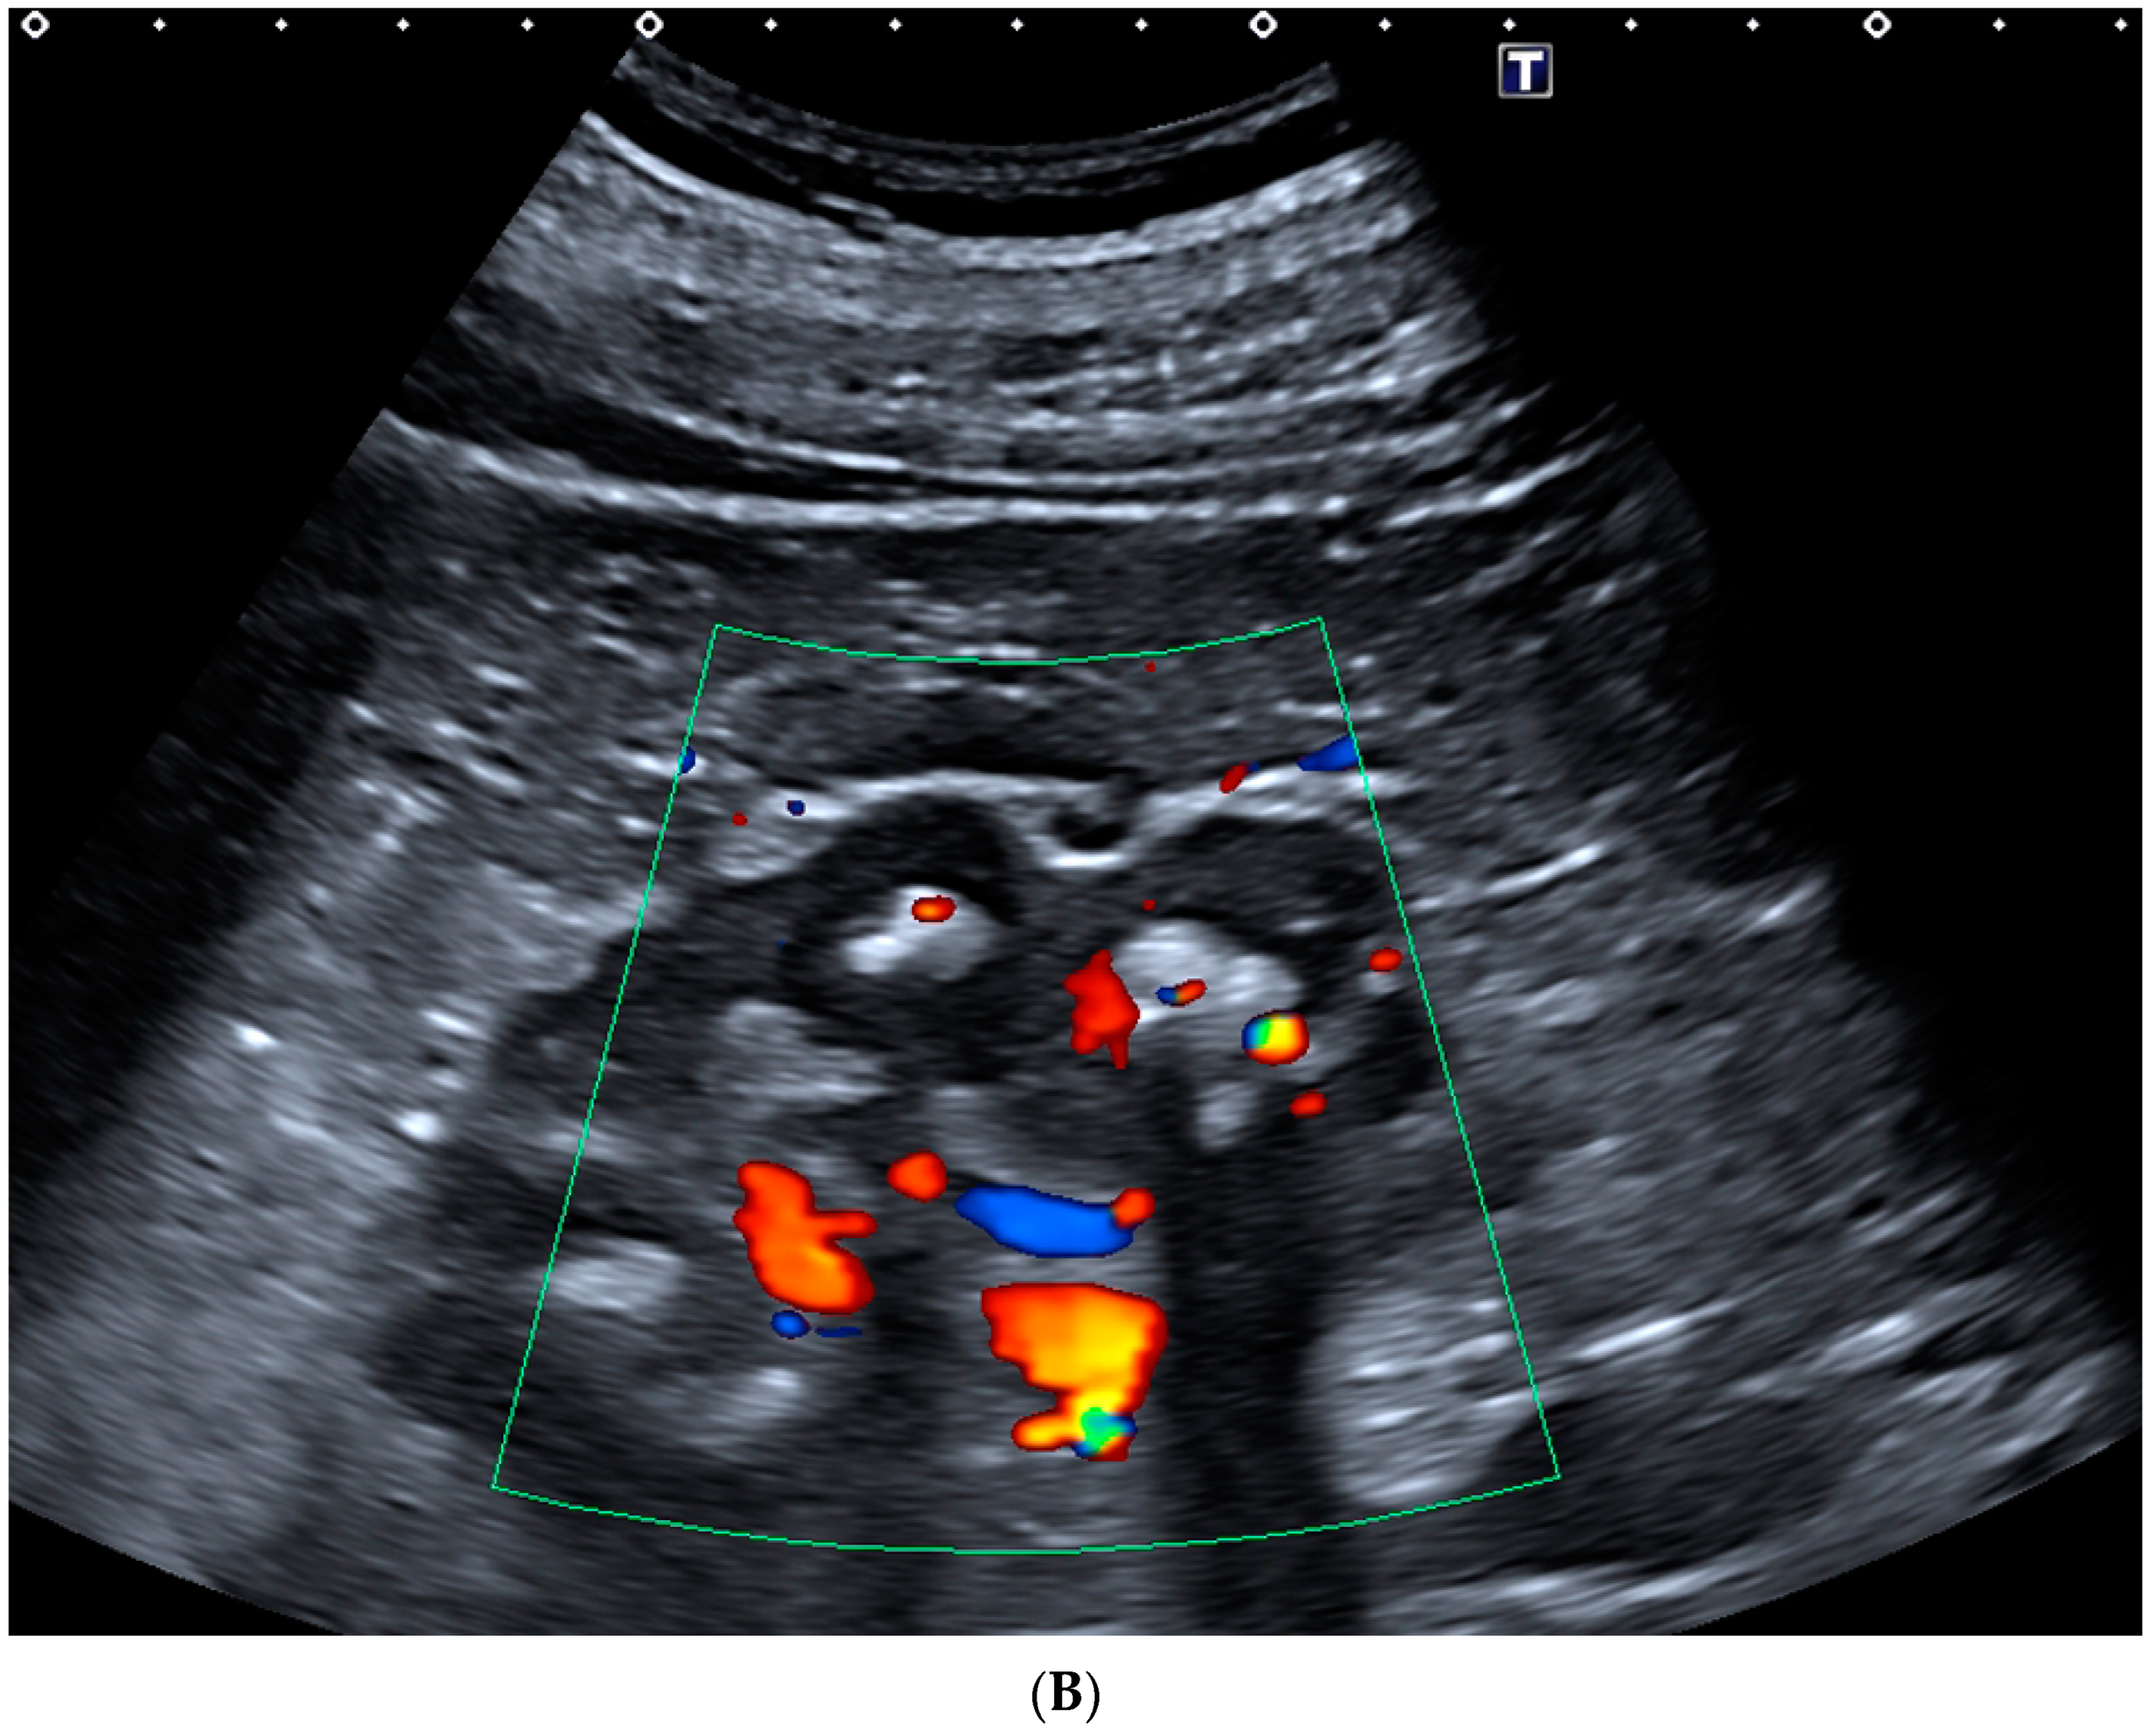

- Rahmouni, A.; Bargoin, R.; Herment, A.; Bargoin, N.; Vasile, N. Color Doppler twinkling artifact in hyperechoic regions. Radiology 1996, 199, 269–271. [Google Scholar] [CrossRef] [PubMed]

- Abdel-Gawad, M.; Kadasne, R.D.; Elsobky, E.; Ali-El-Dein, B.; Monga, M. A prospective comparative study of color Doppler ultrasound with twinkling and non-contrast computerized tomography for the evaluation of acute renal colic. J. Urol. 2016, 196, 757–762. [Google Scholar] [CrossRef] [PubMed]

- Hanafi, M.Q.; Fakhrizadeh, A.; Jaafaezadeh, E. An investigation into the clinical accuracy of twinkling artifacts in patients with urolithiasis smaller than 5 mm in comparison with computed tomography scanning. J. Fam. Med. Prim. Care 2019, 8, 401–406. [Google Scholar] [CrossRef]

- Shang, M.; Sun, X.; Liu, Q.; Li, J.; Shi, D.; Ning, S.; Cheng, L. Quantitative Evaluation of the Effects of Urinary Stone Composition and Size on Color Doppler Twinkling Artifact: A Phantom Study. J. Ultrasound Med. 2016, 36, 733–740. [Google Scholar] [CrossRef]

- Bardin, T.; Tran, K.M.; Nguyen, Q.D.; Sarfati, M.; Richette, P.; Vo, N.T.; Bousson, V.; Correas, J.-M. Renal medulla in severe gout: Typical findings on ultrasonography and dual-energy CT study in two patients. Ann. Rheum. Dis. 2018, 78, 433–434. [Google Scholar] [CrossRef]